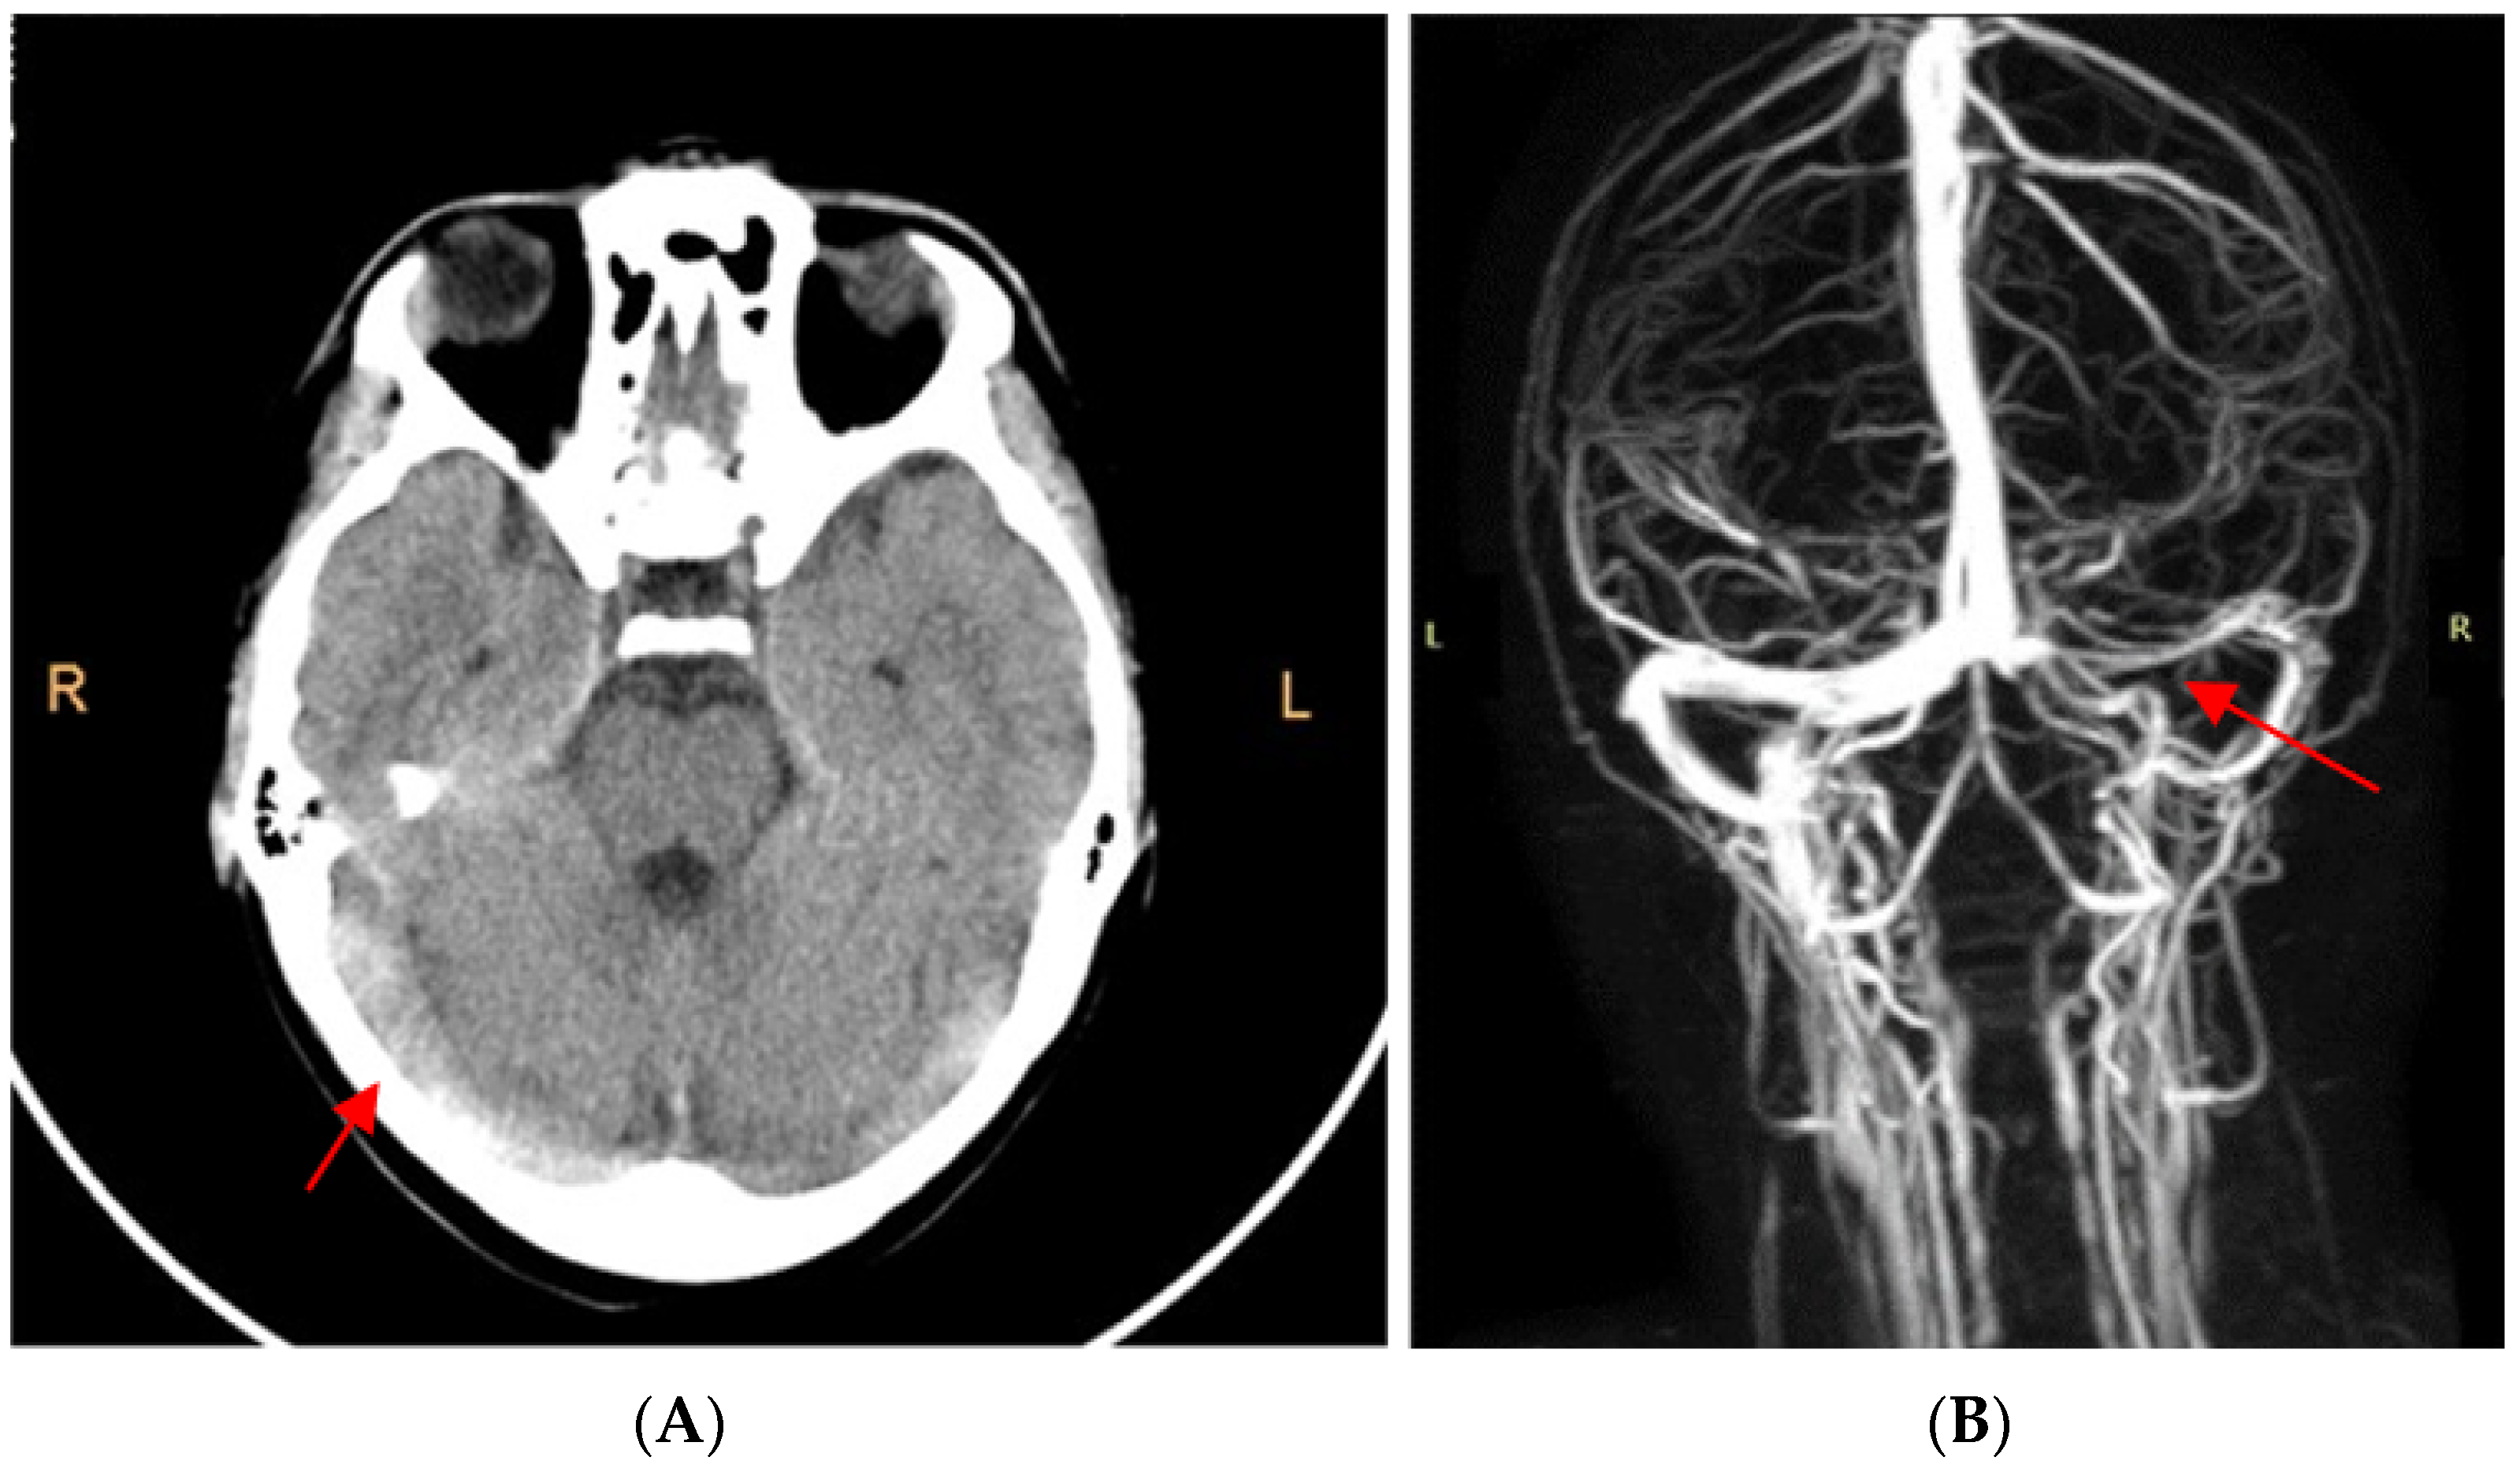

2. Case Report